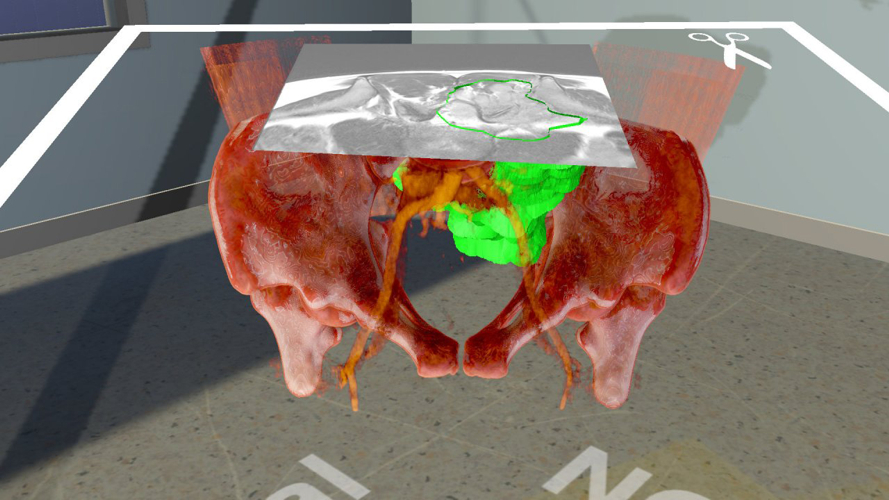

The digital operating room is increasingly becoming a reality with the emergence of new technologies, such as augmented reality and robotic assisted surgery. Three-dimensional planning and current visualisation techniques should lead to custom-made, 3D-printed implants and structural allografts on site. In collaboration with the Technical University of Munich, new visualisation techniques for instrument navigation and augmented reality for surgical procedures will be investigated. The visualisation of three-dimensional planning scenarios on remote locations is also the focus of a collaboration with the university of Basel, which aims to introduce a virtual-reality-based planning tool. Together with the University of Rennes, current robot-assisted surgery is being analysed in terms of workflow, ergonomics and efficiency. In a further collaboration led by the Polytechnic University of Turin, a network of doctoral students is being established, which includes several universities, such as the University of Cádiz and the Free University of Brussels, as well as a number of medical device companies. There is also a focus on improving techniques for filling bone defects, with the aim of increasing allograft stability in difficult revision cases. The mechanical properties of allografts have been improved by optimising grain size distribution, liquid content and impaction procedure. Usability and biomechanical investigations have been conducted to improve techniques and instruments for bone removal procedures.